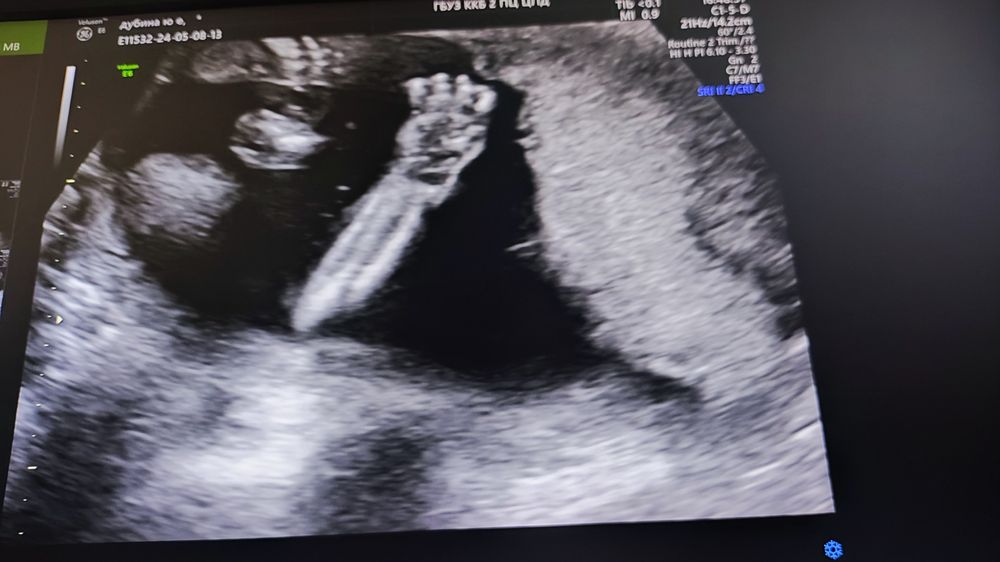

20 недель, скрининг)

Анализы, скринингиНу вот и прошла половина беременности! Врываемся во вторую с четкой уверенность что у нас сынок! Все хорошо, нишу мою не нашли, которая была, шейка 45 мм) все показатели в норме!

Больше волновалась, узистка попалась волшебная, и фото дала сделать и видео снять)